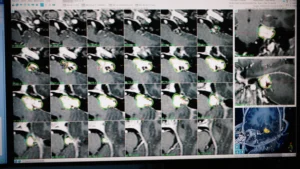

La intersecția dintre tehnologie și îngrijire medicală, ICCO EMS oferă echipamente și servicii inovatoare pentru neurochirurgie, radioterapie, radioprotecție, iradiere sânge și recuperare medicală.

Furnizăm echipamente medicale avansate, selectate pentru performanță, siguranță și fiabilitate în domenii critice precum oncologia, radioterapia și neurochirurgia.